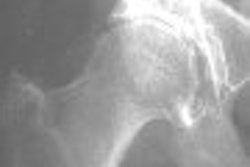

The concordance -- or lack of same -- between x-ray and MRI in imaging patients with hip dysplasia was the subject of research presented at the International Society for Magnetic Resonance in Medicine (ISMRM) meeting in Seattle. Staff writer Shalmali Pal was on hand to report on the presentation, which is the subject of this edition's Insider Exclusive.

In the study, the researchers compared MRI and radiography measurements of key elements of hip anatomy in patients with developmental dysplasia of the hip (DDH). They found that MRI and x-ray measurements agreed in only one of four categories used to measure hip dysplasia. Find out the implications of their research for patient management by clicking here.